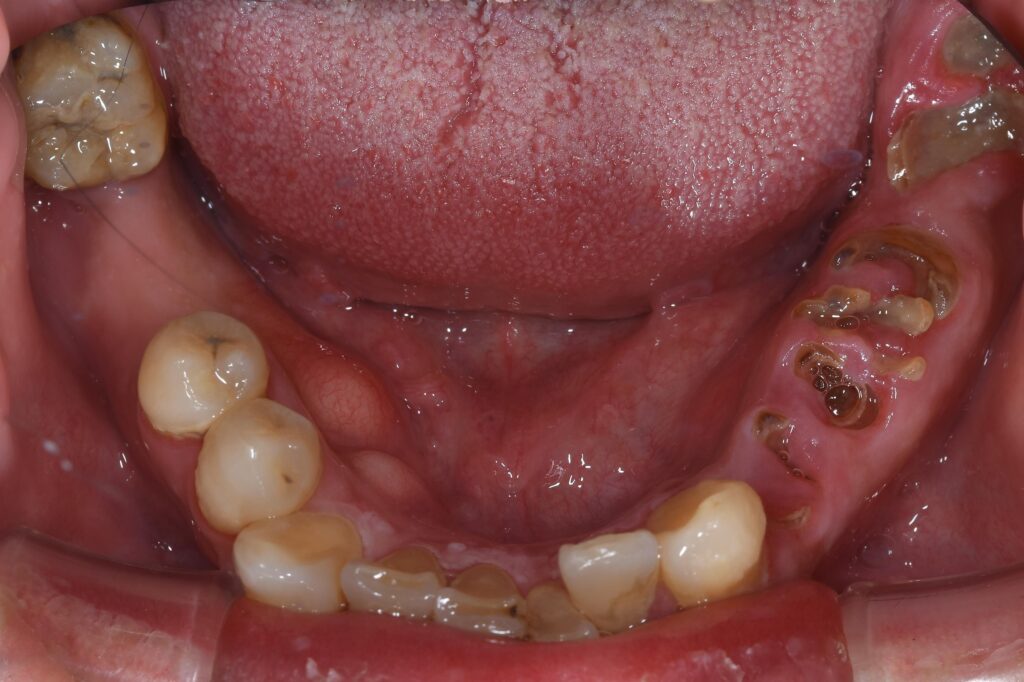

今回はセラミック(ジルコニア)・インプラントを行った全顎治療の患者様の1例です。まずは初診時の状態です。

【初診時】

問題点を列挙していきます。

【問題点】

①長期間歯科医院の来院がなく、歯周病・虫歯が重度に進行した。

②下顎前歯に位置が逸脱した歯牙が存在する。

③奥歯を喪失すると歯全体の支え(大黒柱)がなくなり、前歯がどんどん崩壊する。

簡略的には上記が問題点となります。